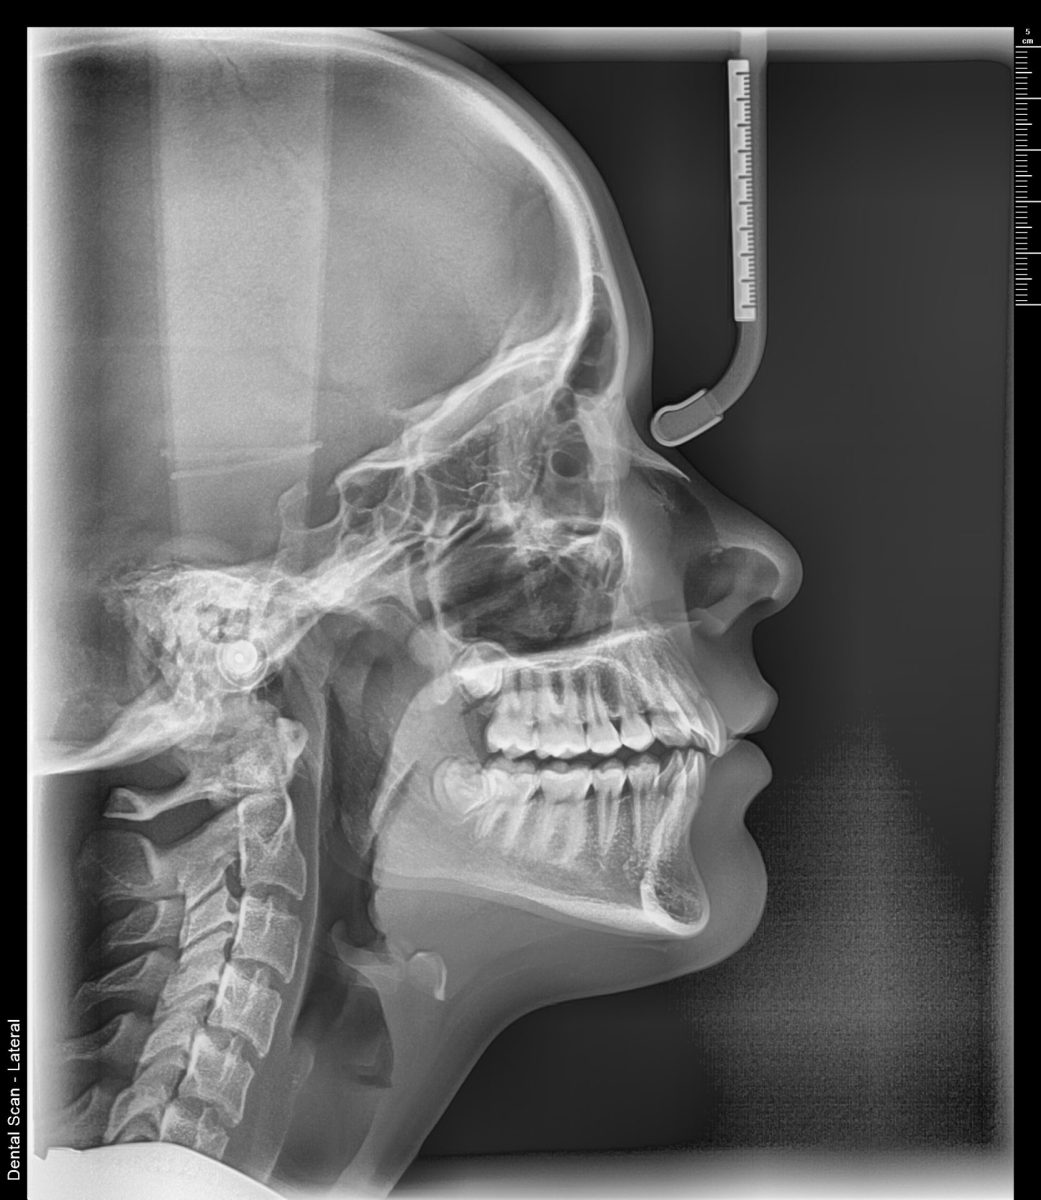

Lateralni cefalogram – bočni prikaz glave i vilice

Lateralni cefalogram (Lateralni Kefalogram ili Telerendgen) je bočni radiografski snimak glave i vilice koji pruža detaljne informacije o odnosima između zuba, vilica i kostiju lica. U Dental Scan centru koristimo ultra HD digitalnu tehnologiju koja omogućava visoku rezoluciju uz minimalnu dozu zračenja, a snimanje se obavlja brzo i bez zakazivanja.